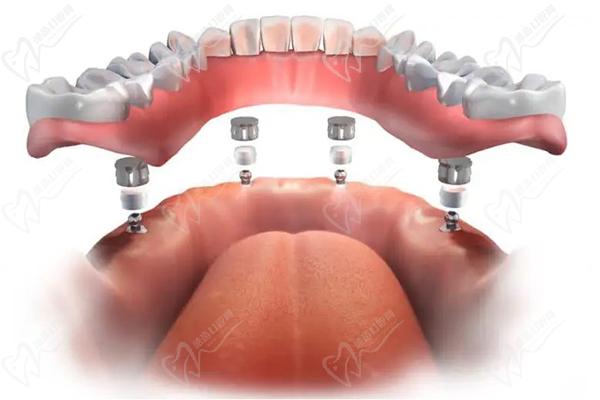

作為廣州市實力強勁的綜合性口腔醫(yī)院,暨南大學穗華口腔在種植牙領(lǐng)域名聲在外。醫(yī)院擁有一批經(jīng)驗豐 富的種植醫(yī)生,例如馮智強醫(yī)生,并擅長各種種植牙手術(shù),包括單顆種植、多顆種植、微創(chuàng)種植、數(shù)字化種植、半口/全口種植,甚至難度技術(shù)高的穿顴穿翼種植。

半口種植牙·集采種牙:21860元起

全口種植牙·集采:42720元起